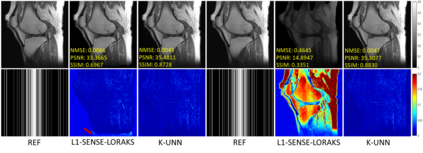

Recently, untrained neural networks (UNNs) have shown satisfactory performances for MR image reconstruction on random sampling trajectories without using additional full-sampled training data. However, the existing UNN-based approach does not fully use the MR image physical priors, resulting in poor performance in some common scenarios (e.g., partial Fourier, regular sampling, etc.) and the lack of theoretical guarantees for reconstruction accuracy. To bridge this gap, we propose a safeguarded k-space interpolation method for MRI using a specially designed UNN with a tripled architecture driven by three physical priors of the MR images (or k-space data), including sparsity, coil sensitivity smoothness, and phase smoothness. We also prove that the proposed method guarantees tight bounds for interpolated k-space data accuracy. Finally, ablation experiments show that the proposed method can more accurately characterize the physical priors of MR images than existing traditional methods. Additionally, under a series of commonly used sampling trajectories, experiments also show that the proposed method consistently outperforms traditional parallel imaging methods and existing UNNs, and even outperforms the state-of-the-art supervised-trained k-space deep learning methods in some cases.